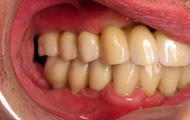

Exemple de 3 dents manquantes remplacées par 3 couronnes sur implants.

Pose des piliers prothétiques et des 3 couronnes scellées.

Situation clinique terminée